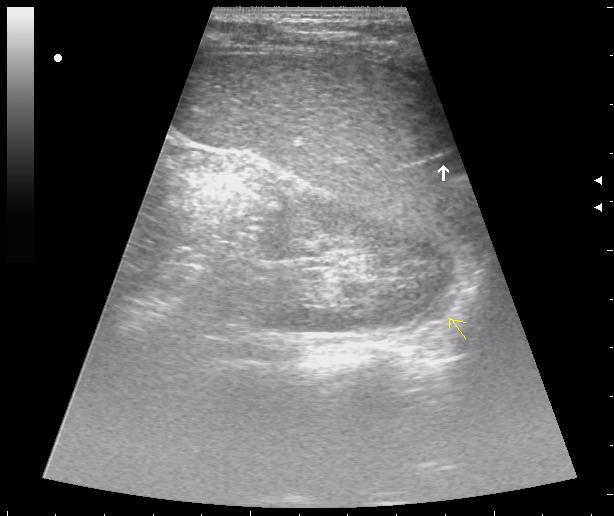

>желтой стрелкой - это левый надпочечник?

Похоже.

Он обычно располагается больше кнутри от верхнего полюса почки и может досигать ее ворот.

Надежнее визуализировать ЛН из позиции, которую я показывал в известной Вам теме.

мальчик лежал на спине (переломы костей таза). на затёки крови не похоже.